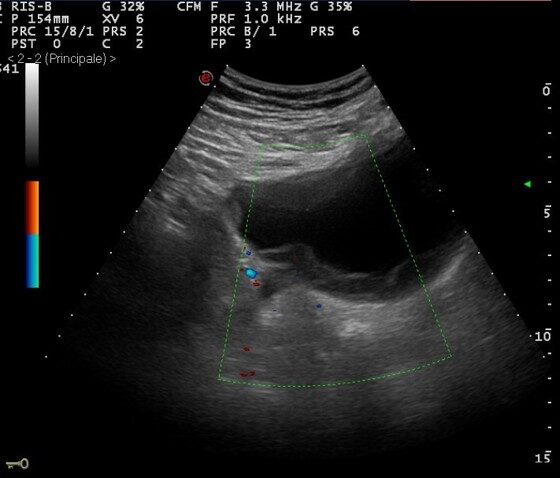

Dr. Babic explains that patients usually had no symptoms or so-called total painless hematuria, the presence of blood in the urine. The disease is usually diagnosed during routine ultrasound examinations.

Dr. Uroš Babić: “ The changes are quite clear and recognizable on ultrasound. When something suspicious is noticed on the ultrasound examination, a further diagnostic algorithm is taken. The next is a cystoscopic examination. It is an endoscopic examination that involves the introduction of an endoscopic device, through the urethra, into the bladder. The “naked eye” recognizes possible changes in the bladder, and then, based on the aspect, location and size, it is assessed whether it is necessary to do something else from the diagnostics, and that is a scanner or magnetic resonance imaging. After that, further treatment is planned. ”